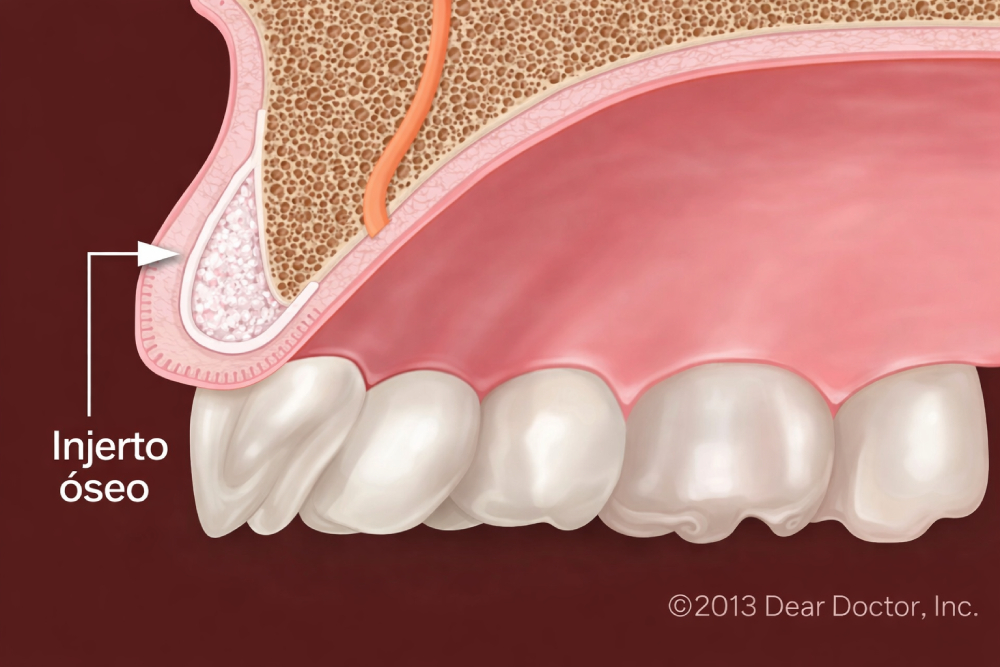

El injerto óseo es un procedimiento quirúrgico menor que normalmente se realiza en una clínica dental. Se realiza una incisión en la encía para acceder al hueso subyacente y luego se añade el material de injerto. En la mayoría de los casos, el material de injerto consiste en minerales óseos procesados alrededor de los cuales el cuerpo depositará nuevas células óseas.

El material de injerto puede provenir del propio cuerpo del paciente, pero con frecuencia se utiliza hueso de un animal o de un donante humano que ha sido tratado en un laboratorio para garantizar su esterilidad y seguridad. Incluso puede ser una sustancia sintética. El material de injerto se presenta en diversas formas: polvo, gránulos, pasta o un gel que se puede inyectar con una jeringa. El injerto, que generalmente se cubre con una membrana de colágeno para optimizar la regeneración ósea, actuará como una estructura sobre la cual el cuerpo construirá hueso nuevo.